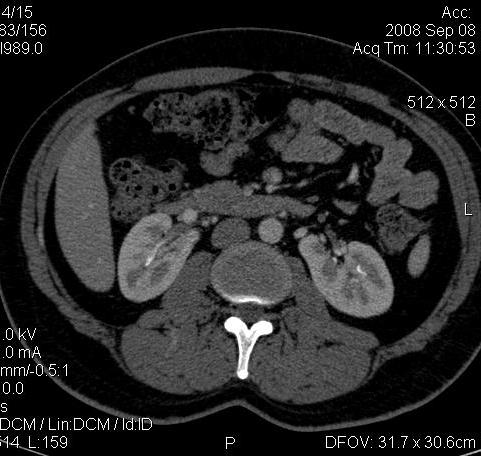

Ну ладно, раз никто больше не хочет, то отвечу свою версию - аномалия развития - подковообразная почка (horseshoe kidney).

Да красивая подковообразная почка - встречала раз 6-7.

Не вызывает сомнений. Картинка замечательная. Должно быть хорошо видно и на УЗИ.

Для невладеющего КТ,очень четка видна аномалия на 3-4х снимках.А вот на 4-м скане в проксим.сегменте цистоида тоже есть гиперденсное точечное образование-не камень случайно?